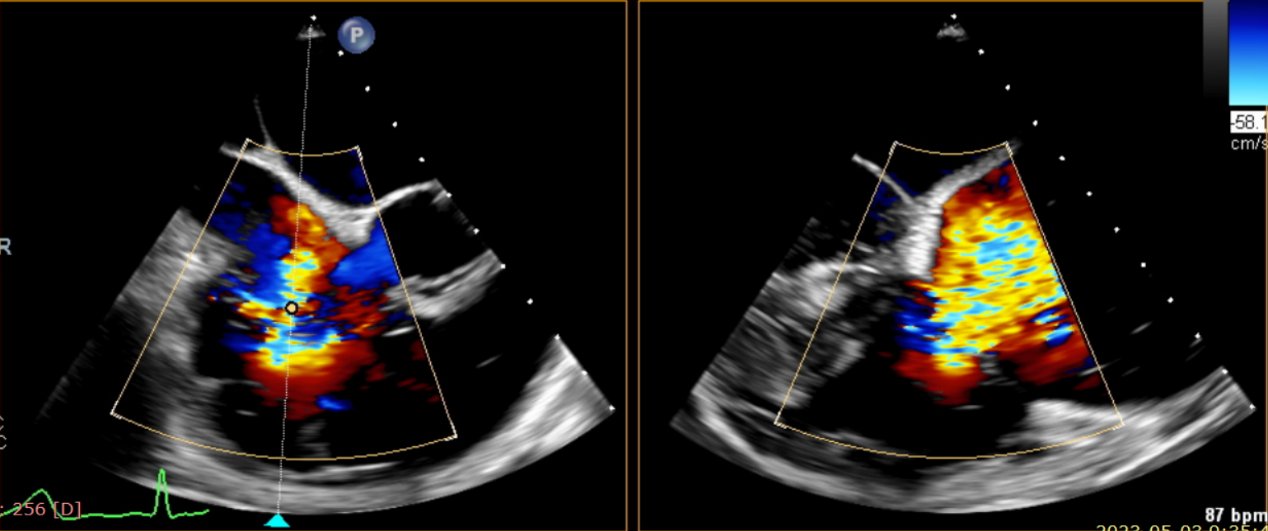

術(shù)前超聲提示大量三尖瓣反流

術(shù)中輸送器在超聲引導(dǎo)下調(diào)整位置

術(shù)后超聲提示僅殘余輕微瓣周漏